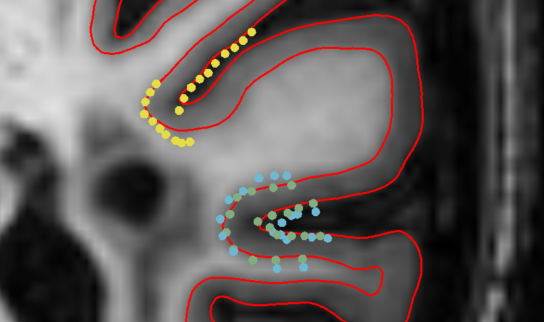

5.4 Consistency of reconstructed points

Refer to caption

Fig. 5: Analysis of the consistency of correspondences with respect to the position (top) and thickness (bottom) on the test-retest dataset. We plot the root-mean-square deviation (RMSD) of vertex positions per surface and thickness measurements per hemisphere from the respective average in the 40 scans per subject (ignoring thickness measures from the ”undefined” middle region). Violin plots represent kernel density estimates of the per-vertex values for V2C-Flow and FreeSurfer (v7.2) with horizontal lines at respective quartiles. Surface renderings show the RMSD per vertex for left WM surfaces. All values are in mm.

The results in the previous sections validated the applicability of V2C-Flow for cortical surface reconstruction. Now, we evaluate the consistency of reconstructed points. It is an essential prerequisite for the surfaces to be comparable on a per-vertex basis, ultimately enabling the study of anatomical changes over time or among different populations. Intuitively, the same template vertex should be moved to the same location when provided with different scans of the same subject (given that the scans were acquired within a short period of time to be not susceptible to structural changes). Although this potential represents a major advantage of mesh-based surface reconstruction methods over segmentation- or SDF-based approaches [17], it has not been explored nor validated for cortex reconstruction so far. We close this gap and evaluate the geometric correspondence of reconstructed points and accompanied cortical thickness measurements in V2C-Flow using a public test-retest (TRT) dataset [36] that contains 40 scans from three subjects, respectively, acquired within one month. We compare the results to FreeSurfer [10], which implements the standard approach for vertex-wise comparison of different cortical meshes. In a nutshell, FreeSurfer inflates the surfaces to a sphere, registers them based on curvature, and resamples the surfaces to have the same number of vertices. We use the standard fsaverage template for both methods.

On the left WM surfaces in Figure 5, we plot the root-mean-square deviation (RMSD) of vertex positions and thickness measurements per vertex from the respective mean values for each subject in the TRT dataset. In addition, we show violin plots and quartiles of the RMSD per hemisphere for all surfaces. It can be observed that the consistency of extracted points in terms of RMSD is slightly better in V2C-Flow compared to the registration-based FreeSurfer pipeline. This is in particular remarkable since we used the raw V2C-Flow output without registration or resampling. Similarly, the cortical thickness measurements associated with each vertex are slightly more consistent in V2C-Flow than in FreeSurfer in terms of RMSD from the average thickness per vertex. It stands out that the variation in vertex locations is considerably higher (up to 5mm) than the variation in thickness measurements (up to 1.5mm). A likely source for this difference is variations in the scanning procedure that were not compensated by registering the MRI scans to MNI space.